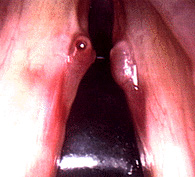

Close up of vocal fold nodule

The picture to the left shows typical vocal fold nodules. (Anterior is to the top, and posterior is the back. Note that they are present on both vocal folds and in this case are actually quite symmetric. The are located about one-third of the way back on the vocal folds.